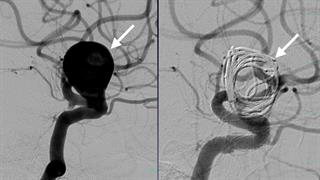

"Ευαγγελισμός": Πώς έσωσαν 46χρονη μητέρα από εγκεφαλική αιμορραγία

Παρουσίασε υπαραχνοειδή αιμορραγία, που προκλήθηκε από ανεύρυσμα εγκεφάλου.